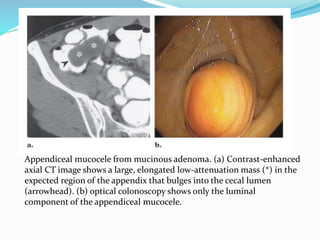

This document discusses colorectal polyps. It defines polyps and describes their types, including neoplastic and non-neoplastic polyps. It discusses adenomatous polyps in depth, noting their malignant potential increases with size over 1cm and villous architecture. Radiological diagnostic methods for polyps including single and double contrast barium enema and CT colonography are explained. The document provides an overview of polyp pathogenesis and genetic syndromes like FAP that increase cancer risk.